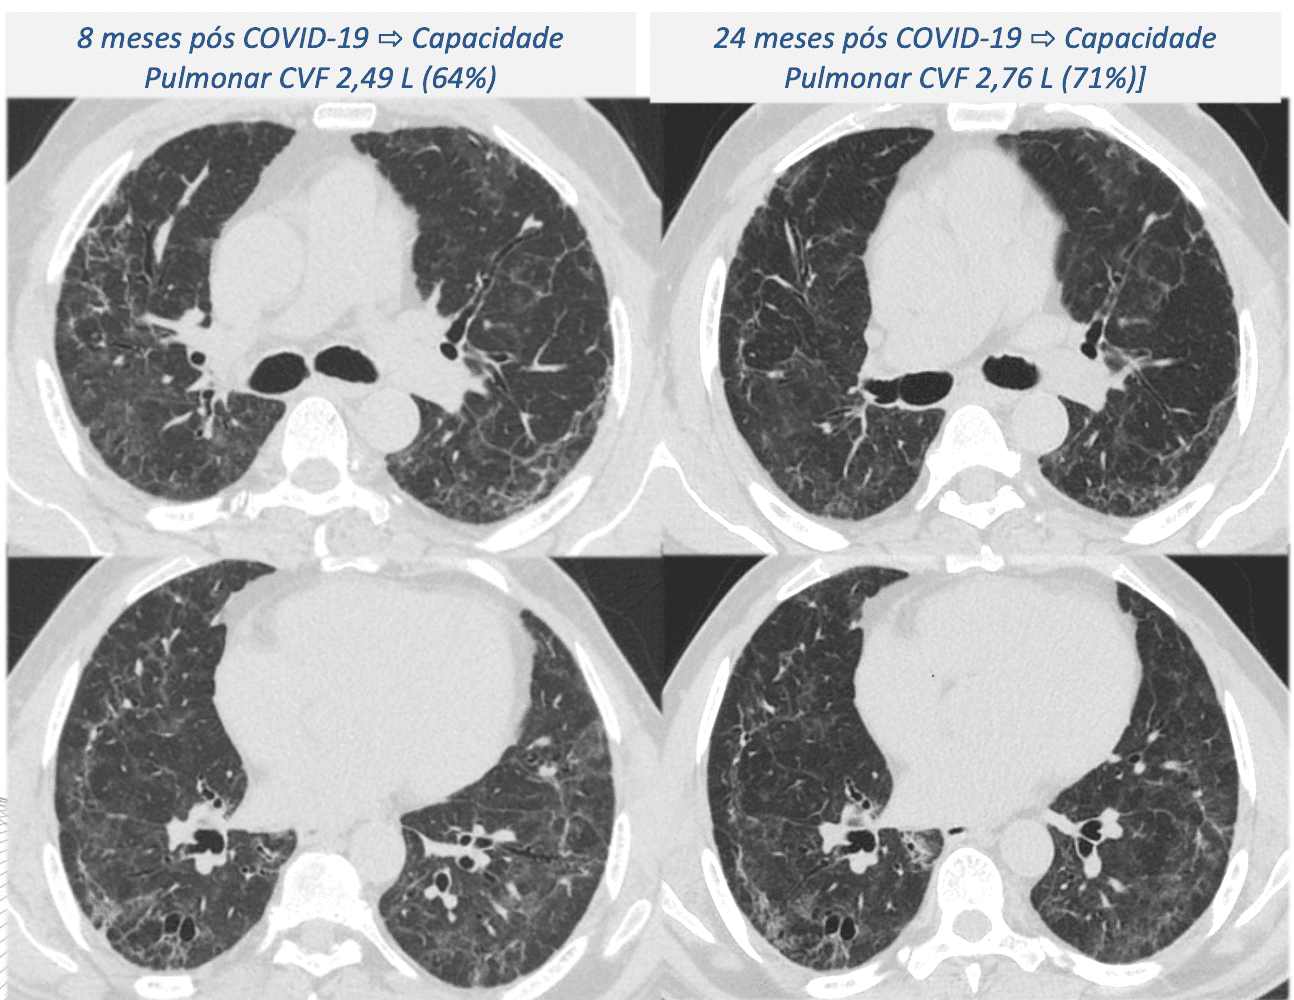

Dois anos após a alta hospitalar, a maioria dos pacientes que tiveram COVID-19 grave e precisaram ser intubados está apresentando sequelas pulmonares de longo prazo. Alguns indivíduos que tiveram uma boa recuperação após a doença também estão manifestando piora no quadro 24 meses após a internação. Um estudo realizado no Hospital das Clínicas da Faculdade de Medicina da Universidade de São Paulo (HC-FM-USP) revela que 91% dos 237 pacientes monitorados apresentaram alguma alteração pulmonar após dois anos, sendo 58% casos de inflamação e 33% de fibrose. Entre os que tiveram lesões semelhantes à fibrose, 2% apresentaram melhora e 25% piora.

Os pesquisadores alertam para a preocupação com a fibrose pulmonar, cuja evolução pode ser bloqueada através de tratamentos com medicamentos como corticoides ou antifibróticos. Existem mais de 200 fatores que podem levar à formação de cicatrizes e fibrose pulmonares, sendo a frequência maior em casos de COVID-19. O estudo também identificou pacientes evoluindo para bronquiolite, uma doença nas pequenas vias aéreas, e ressalta a importância de novos protocolos de tratamento.